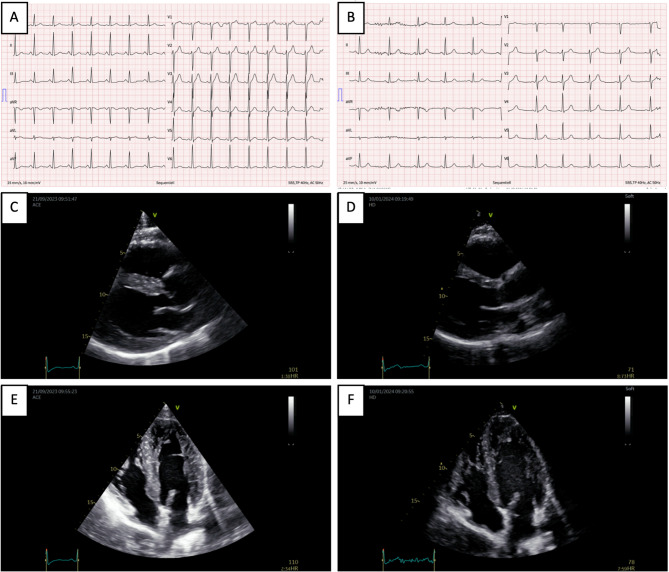

Introduction: The non-medical use of androgens among recreational gym users has become a global substance use concern. Complications from use particularly appear to affect the cardiovascular system, including the development of cardiovascular events, as well as anabolic steroid-induced cardiomyopathy (ASIC). Furthermore, the development of substance dependence with a specific withdrawal syndrome appears to be common and is contributed by the development of endocrine dysfunction related to anabolic steroid-induced hypogonadism. A 38-year-old male law enforcement officer and recreational bodybuilder presented with multiple health complaints following years of supraphysiologic androgen use and polypharmacy. Key symptoms included new-onset subacute dyspnea, dizziness, palpitations, headaches, and recurrent failed attempts at androgen cessation. Clinical findings showed abnormal blood pressure, testicular atrophy, plethoric appearance, and laboratory evidence of progressive polycythemia (hematocrit: 56.9%; normal < 49%), elevated testosterone, and suppressed luteinizing and follicle-stimulating hormones. He was at risk for muscle dysmorphia and met criteria for androgen dependence. Diagnosis confirmed ASIC. Treatment consisted of recurrent bloodletting for polycythemia, guideline-based cardiac management, and a structured endocrine regimen (tapered transdermal testosterone, oral Tamoxifen, subcutaneous human chorionic gonadotropin) to support androgen discontinuation and hormonal recovery. At 4 months, ASIC had normalized, and he was asymptomatic. However, after 6 months, he developed laboratory-confirmed idiopathic primary hypogonadism and began guideline-directed testosterone replacement. Despite more than a year of abstinence from non-medical androgen use and normalization of cardiac function, the patient died from a cardiovascular event, highlighting the possibly persistent risks of prior androgen use.